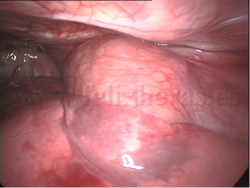

Biopsia de tumores de mediastino

Linfoma de mediastino anterior